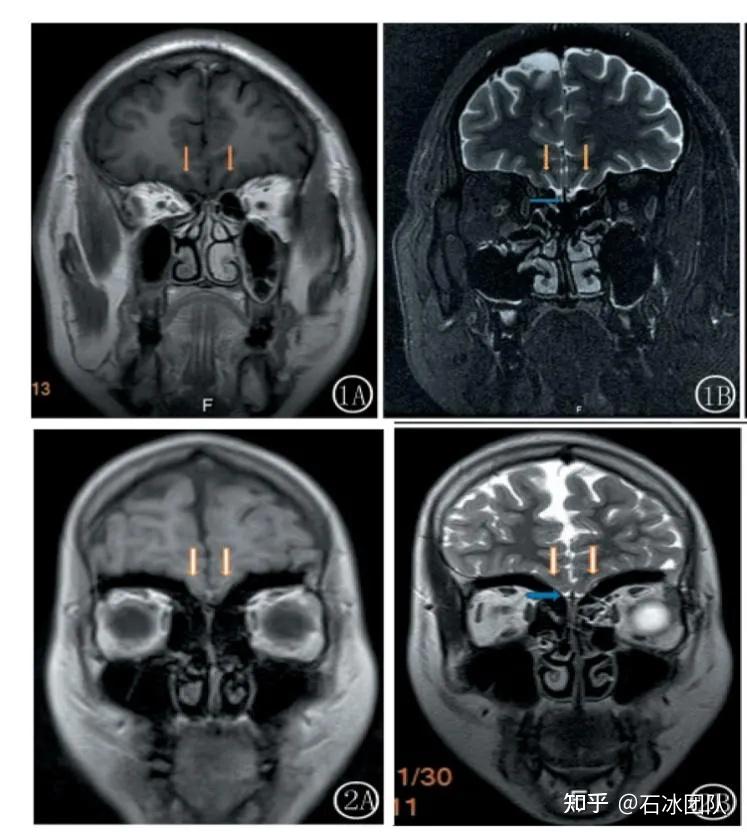

卡尔曼综合征

卡尔曼氏综合征

kallman综合征ppt课件

kallman综合征